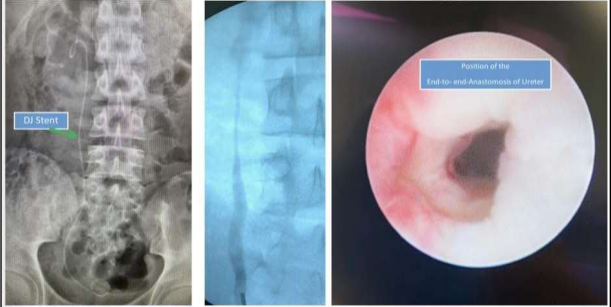

After spatulation of both ureter ends and insertion of a DJ stent, I completed an end-to-end anastomosis.

The postoperative course and hospital stay proceeded without complications. After four weeks, I removed the DJ stent and performed ureteroscopy with Ureterography.